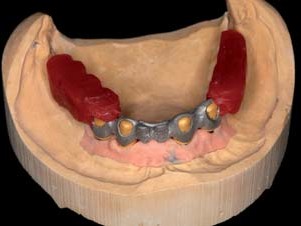

Um die Retentionsflächen zu vergrößern, wurden sie anschließend im Labor mit 120μm Aluminumoxid abgestrahlt (Abb. 15–19). Die individuellen Abutments wurden eingescannt und darauf die Primärteile aus in A3 eingefärbtem Zirkonoxid angefertigt. Design und Herstellung der Zirkonprimärteile erfolgten direkt im Labor (Modellier- Software und Fräseinheit Zirkonzahn, Gais) In der Software wurde die Innenpassung der Primärkronen optimal den jeweiligen Abutments angepasst. Die Parallelität der Teleskope zueinander bzw. die Gesamteinschubrichtung wurden ebenfalls am Bildschirm festgelegt. Die auf einen Konuswinkel von 2 Grad gefrästen Primärteile wurden unter Wasserkühlung im Parallelfräsgerät feingeschliffen und anschließend mit Diamantpolierpaste auf Hochglanz poliert. Eine „spiegelglatte“ Oberflächenqualität der Zirkonoxid-Primärkrone und ein nur minimaler Spalt zwischen Patrize und Matrize von ca. 5 μm sind entscheidend für eine perfekte Funktion. Eine Präzision, die ohne Scannertechnologie und CAD/CAM-Fertigung nicht erzielbar wäre.

Die dadurch erzielte exakte Passung und die hohe Biokompatibilität von Zirkonoxid sind speziell bei Suprakonstruktionen maßgebliche Parameter, um langfristig Komplikationsrisiken in den periimplantären Hart- und Weichgewebestrukturen vermeiden zu können (Abb. 20–21). Die Sekundärteile wurden direkt auf den Zirkonprimärteilen galvanisch abgeschieden. Mit der Galvanotechnik lassen sich hoch präzise und passgenaue Feingoldmatrizen anfertigen, die wesentlich zur lagesicheren Fixierung des Prothesenkörpers beitragen.⁴ Bei der Galvanisierung war unbedingt darauf zu achten, die Schicht Silberleitlack gleichmäßig und nicht zu dick aufzutragen. Hierfür hat sich aus Sicht der Autoren die Airbrush-Technik als alternativlos herausgestellt. Anderenfalls könnte es bereits nach kurzer klinischer Funktionszeit zu einem Haftungsverlust kommen, da die Matrize nur noch punktuell mit der Patrize Kontakt hat. Solche mittels Galvanotechnik hergestellten Sekundärteile für Konusprothesen sind seit über zehn Jahren etabliert.⁶ Die Tertiärstruktur wurde für den Ober- wie den Unterkiefer aus einer Nichtedelmetalllegierung herkömmlich im Modellgussverfahren hergestellt. Noch auf dem Meistermodell wurde das Gerüst auf einen spannungsfreien Sitz hin kontrolliert und mit